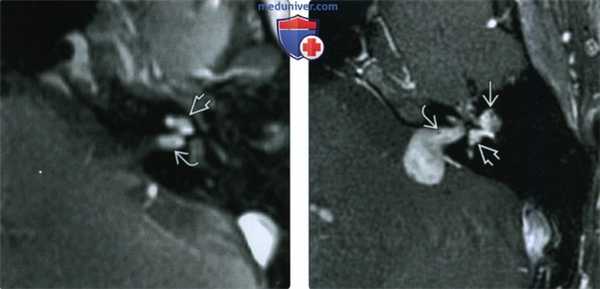

(Слева) При аксиальной МРТ Т1 ВИ без контрастного усиления определяются классические признаки интралабиринтного кровоизлияния (ИЛК): кровь с гиперинтенсивным сигналом (метгемоглобин) в перепончатом лабиринте улитки, преддверии и полукружных каналах.

(Справа) При аксиальной МРТ Т2 ВИ у этого же пациента определяется гиперинтенсивный Т2 сигнал во внутреннем ухе. Сигнал в ИЛК на Т2 ВИ варьирует в зависимости от возраста крови. При снижении интенсивности сигнала диффузное поражение лабиринта помогает отличить ИЛК от интралабиринтных опухолей.

(Слева) При аксиальной МРТ Т1 ВИ без контраста на уровне внутренних слуховых каналов определяется гиперинтенсивный сигнал в перепончатом лабиринте внутреннего уха слева, обусловленный интралабиринтным кровоизлиянием (ИЛК). Сравните его с нормальным жидкостным сигналом справа.

(Справа) При корональной МРТ Т1 ВИ FS у этого же пациента определяется, что гиперинтенсивный сигнал во внутреннем ухе слева не обусловлен жиром, поскольку он сохраняется несмотря на подавление сигнала от жира. Изменения исключают интралабиринтную шванному и подтверждают диагноз ИЛК.